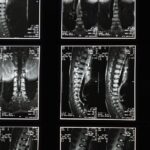

Les symptômes d’un bombement discal incluent des douleurs dans le dos, des raideurs, et parfois des sensations d’engourdissement dans les membres. Il est crucial d’identifier ces symptômes de manière précise, car cela permettra de mieux orienter le traitement. Un diagnostic initial est généralement effectué via des méthodes d’imagerie comme l’IRM.

Examens d’imagerie: Réaliser des IRM ou radiographies pour évaluer l’étendue du bombement discal.

La première étape dans la prise en charge d’un bombement discal est une évaluation complète par un professionnel de santé. Cela implique un examen physique suivi de tests d’imagerie comme les IRM ou les radiographies. Ces examens aident à déterminer la gravité du bombement et à exclure d’autres affections, telles que les hernies discales. Une description détaillée des symptômes est également cruciale, car elle permettra de mieux cibler le traitement.

Un traitement efficace commence par un diagnostic précis établi par un professionnel de la santé. Souvent, ce diagnostic utilise des examens d’imagerie, comme une IRM, pour évaluer la gravité du bombement discal et déterminer son impact sur les nerfs adjacents. Identifier correctement la condition permet d’établir une approche thérapeutique adaptée, qui pourrait comprendre autant des méthodes conservatrices que des solutions plus avancées.